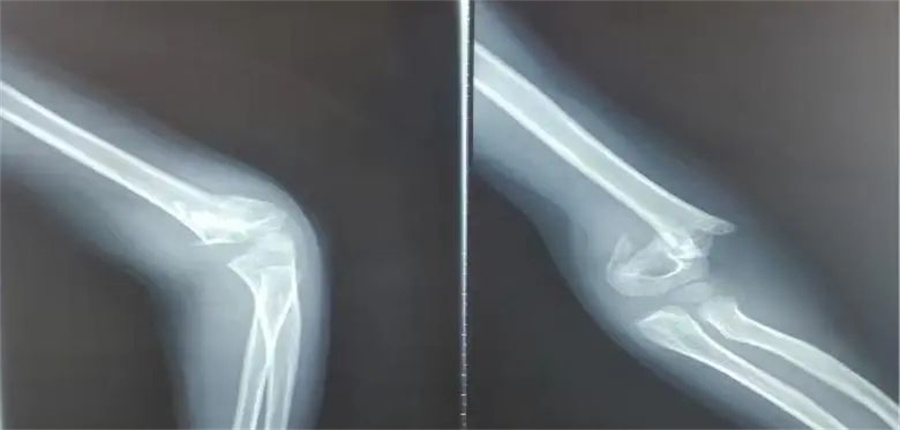

诚瑞的家长赶紧带他来到啪啪网 。入院当天,骨科医生发现,孩子是重度伸直型三度肱骨髁上骨折。

在各项检查指标都正常的情况下,儿童医院骨科的医护人员为他做了髁上骨折闭合复位术。

正常情况下,这属于常规手术。但是由于诚瑞太胖,胳膊又短又粗,复位的时候摸不到骨头,无形中增加了手术难度。

骨科医生在放射线下,一点一点摸索,最终复位成功,并且术后没有切口,没有瘢痕,4天后,孩子顺利出院。